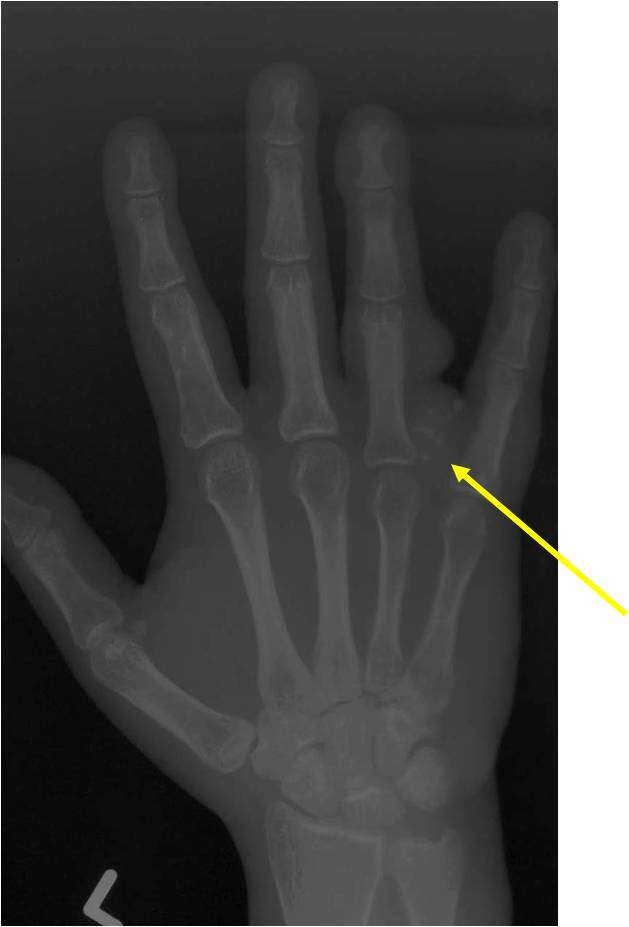

Geographic lesion Stippled calcifications in lesion Phalanx is expanded Significant endosteal scalloping No cortical destruction No soft tissue extension Cortex Scalloped and Expanded